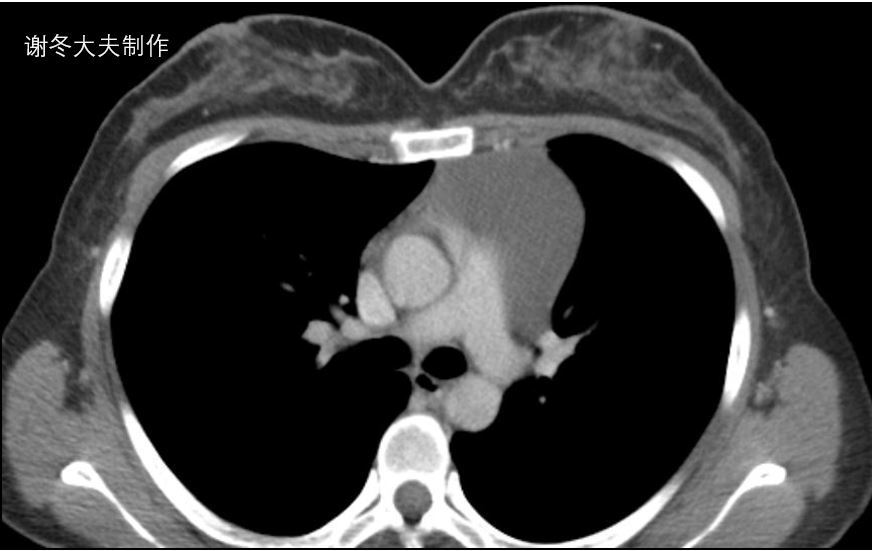

3. 胸腺癌

胸腺鳞癌